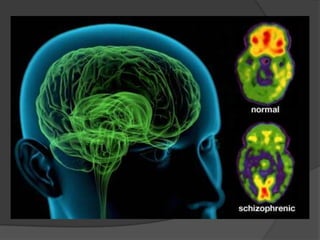

IMAGING IN SCHIZOPHRENIA

Structural imaging



Enlargement of lateral & third ventricles may be static or

progressive.

Frontal lobe abnormalities, particularly prefrontal gray matter

and orbitofrontal regions.

Parietal lobe abnormalities, particularly of the inferior parietal

lobule which includes both supramarginal and angular gyri.

Subcortical abnormalities i.e. cavum septi pellucidum, basal

ganglia, corpus callosum, and thalamus.

All these structural abnormalities may be static or progressive.

Decreased size of medial temporal lobe structures (which

include the amygdala, hippocampus, and parahippocampal

gyrus), and abnormalities of neocortical temporal lobe regions

(superior temporal gyrus).

Hippocampus is not only smaller in size but also functionally

abnormal (disturbed glutamate transmission in functional

scans)

Reduced symmetry in various brain areas may be indicative

of disruption of brain lateralisation during neurodevelopment.

Anatomical & functional deficits in prefrontal cortex.

Volume shrinkage or neuronal loss in medial dorsal nucleus of

thalamus.

Positive symptoms  Decreased volume of

Superior temporal gyrus

Negative symptoms  Enlarged lateral ventricle &

decreased volume of medial temporal lobe

structures

Typical Anti-psychotics  increases the size of the

basal ganglia

Functional imaging

Hypofrontality

Functional scans have also revealed lower levels of

phosphomonoester & inorganic phosphate and higher

levels of phophodiester in schiz pts.

NAA levels were also lower in hippocampus and frontal

lobes in pts with schiz.